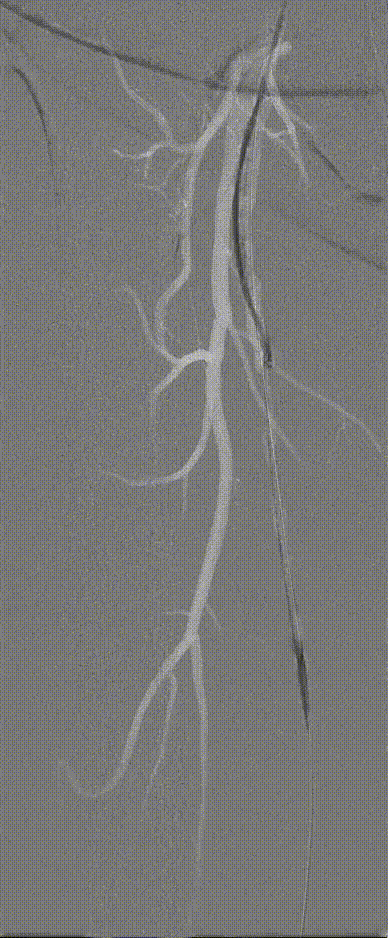

图:造影及通过病变

图:IVUS确认

图:Jetstream 应用

图:DCB 5-250 扩张及全程造影